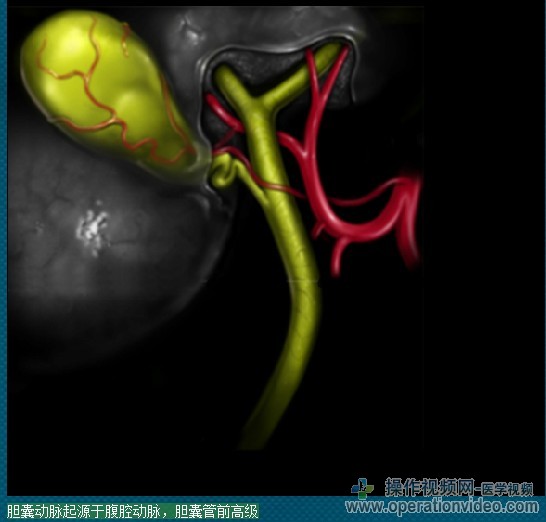

腹腔镜胆总管探查:TRANSCYSTIC方法

一旦达到足够的胆囊管直径,结石可通过以下几种方式是在X线透视或胆道镜指导,或盲目程序中删除。最终的目标是彻底清除胆道结石,避免胆管损伤。他们似乎从胆囊管进入腹腔或逃逸到小囊的腹膜,用纱布垫或内窥镜提取包可以放在后面的肝十二指肠韧带和捕捉结石的胆囊颈部以下的预防结石。

Transcystic胆总管探查术与腹腔镜胆囊切除术中清除CBD中超过75%的患者。它可能是更容易执行比胆总管,特别是在具有小直径的CBD或强烈的炎症的患者。在审查Vecchio和麦克菲迪恩(2002年),“生物多样性公约”的最常见的腹腔镜手术是路线的transcystic。一些外科医生进行腹腔镜胆总管切开,只时的transcystic的方法已经失败。管的胆囊管和“生物多样性公约”的交界处,囊性阀或曲折的胆囊管,胆囊管进入CBD或异常低的插入,或胆总管结石,急性角的位置在近端胆总管结石大于6-7毫米直径,以防止使用这种技术接近胆总管结石的常见因素。